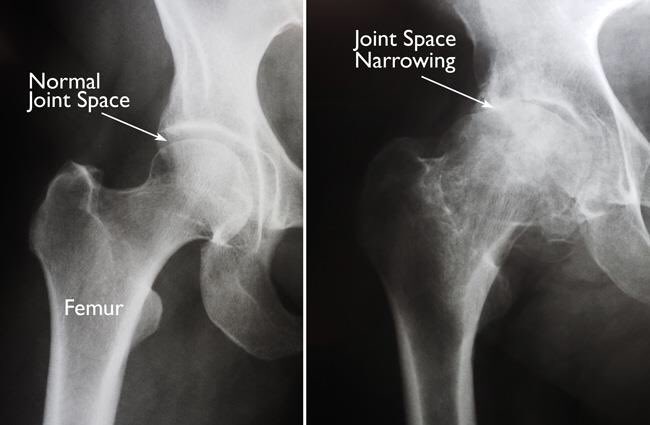

وتبدأ عملية الخشونة والاحتكاك عندما تبدأ طبقة الغضروف المبطن بالتآكل عندها تبدأ عملية التهاب كبسولة المفصل وتكون التشوهات المصاحبة ويبدأ تضيق المفصل في الاشاعة السينية ونلاحظ احتكاك عظمة الفخذ بعظمة الحق